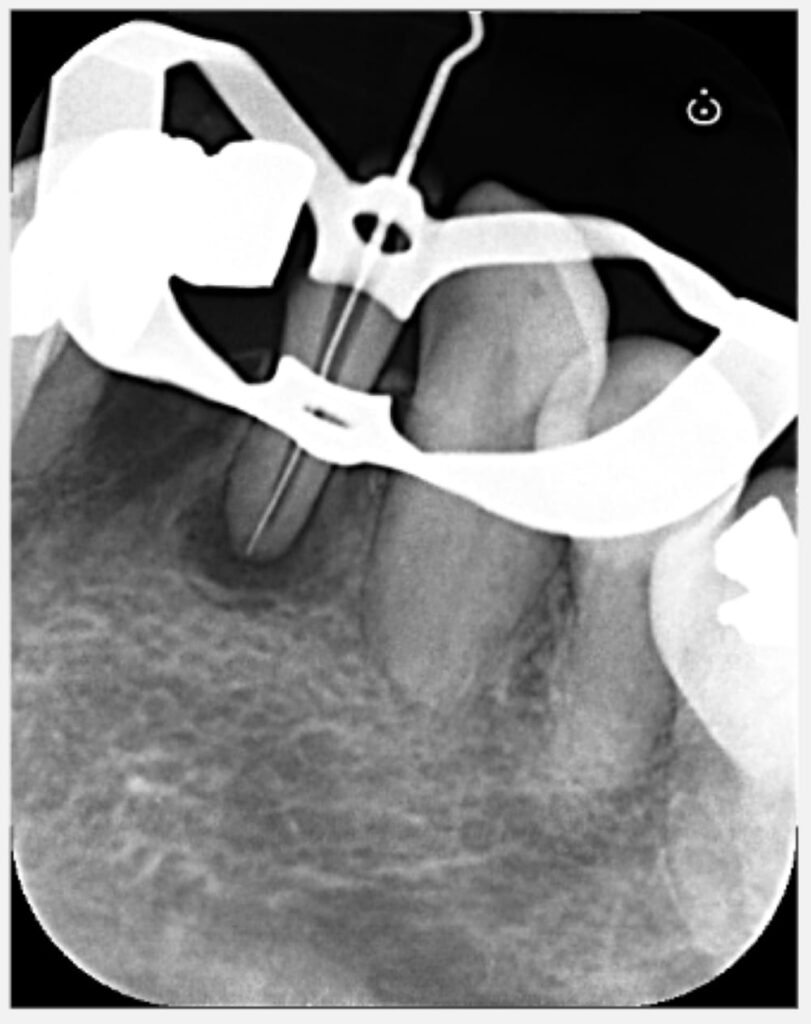

根の先端部分に破折ファイルの断端が確認できたため、除去を試みました。

ステップ2

下顎前歯は根管が細く、除去の難易度も非常に高かったものの、無事にファイルを除去できました。